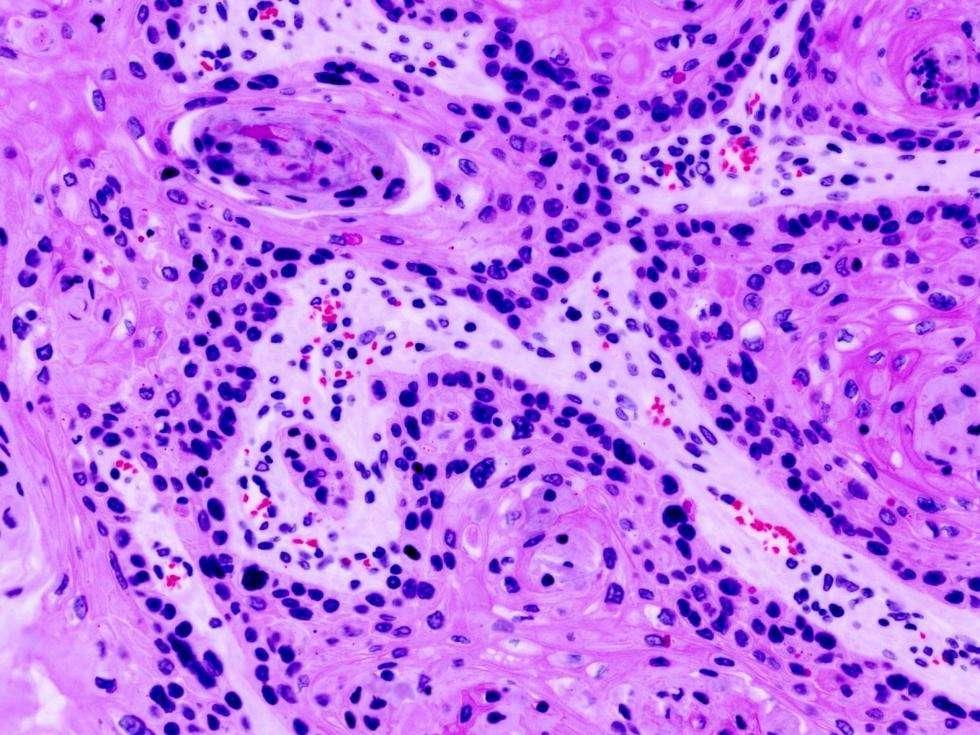

目前,大多数的癌症药物针对的都是肿瘤内普通且数量庞大的癌细胞,但引发癌症的原因并不是这些普通的癌细胞,而是肿瘤干细胞(亦称为肿瘤起始细胞)。它是唯一有产生新癌细胞能力的“起源”细胞,就类似于胚胎干细胞一样。若要根除这些肿瘤干细胞,就必须要标记出它们。目前,英国研究人员已经成功识别和分离出了肿瘤细胞。

研究人员在对人类乳腺癌细胞的实验分析中得出,肿瘤干细胞约占所有癌细胞总数的0.2%。这些干细胞具有很特殊的性质,它们蕴含着巨大的能量并能够迅速增殖。科学家认为,这些干细胞一样可以逃避正常的细胞周期,避免了细胞死亡的自然过程,它们的存在时形成癌症的根本原因。

肿瘤干细胞可以在没有任何组织附着的情况下独立生长,也称之为悬浮生长,而肿瘤的转移方式就是通过血液和淋巴管扩散。这些特点使肿瘤干细胞成为癌症治疗的新目标。目前,科学家们已经能够定位和识别出肿瘤干细胞,下一步将了解其活动规律,进而找到针对肿瘤干细胞的药物。(环球科学“家”限时免费开放中,加入点击>>>)